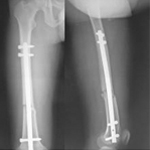

張某,男,50歲,因“左股骨骨不連”入院。植骨+PRP治療后8月完全愈合。

術前